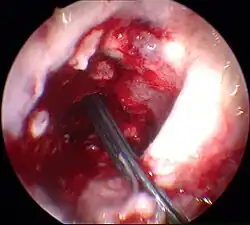

Entfernung der Kreuzbandreste und Bohren der Knochenkanäle

Arthroskopisch werden die Reste des gerissenen vorderen Kreuzbandes entfernt. Dazu wird ein motorgetriebenes Saug-Schneid-Werkzeug (Shaver) und/oder ein Hochfrequenz-(HF)-Ablationsgerät verwendet. Es empfiehlt sich, am Schienbeinkopf einen Rest vom Stumpf zu belassen, um einen Rest von Proprioception zu erhalten und das Eindringen von Gelenkflüssigkeit in den tibialen Kanal zu minimieren. Mit Hilfe eines Zielgerätes wird die Position zur Bohrung eines Kanals durch den Kopf des Schienbeins anvisiert und anschließend gebohrt. Der Durchmesser des Bohrkanals ist dem Durchmesser des Transplantates angepasst. Durch den Kanal des Schienbeins hindurch, oder präziser heute durch einen zusätzlichen anteromedialen Arthroskopiezugang, wird ein Zielgerät für die Bohrung am Oberschenkelknochen angebracht. Mit Unterstützung dieses Zielgeräts wird ein Kanal in den Oberschenkelknochen gebohrt. Dieser Kanal kann sich nach oben verjüngen (Sackloch) und hat eine Länge von etwa 35 mm. Der breitere Teil des Kanals ist für die Aufnahme des Transplantates, der schmalere für den Durchzug der Transplantataufhängung.